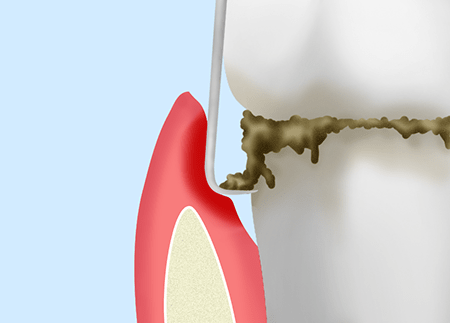

スケーリング

毎日の歯みがきでは落としきれないプラークや歯石を除去します。

ルートプレーニング

スケーリングでは落としきれない歯周ポケットの奥のプラークや歯石を除去してから歯根を滑らかに仕上げます。

歯周ポケットそうは術

局所麻酔を行ったうえで、歯周ポケットの奥深くに入り込んだプラークや歯石、感染歯肉の組織を除去します。